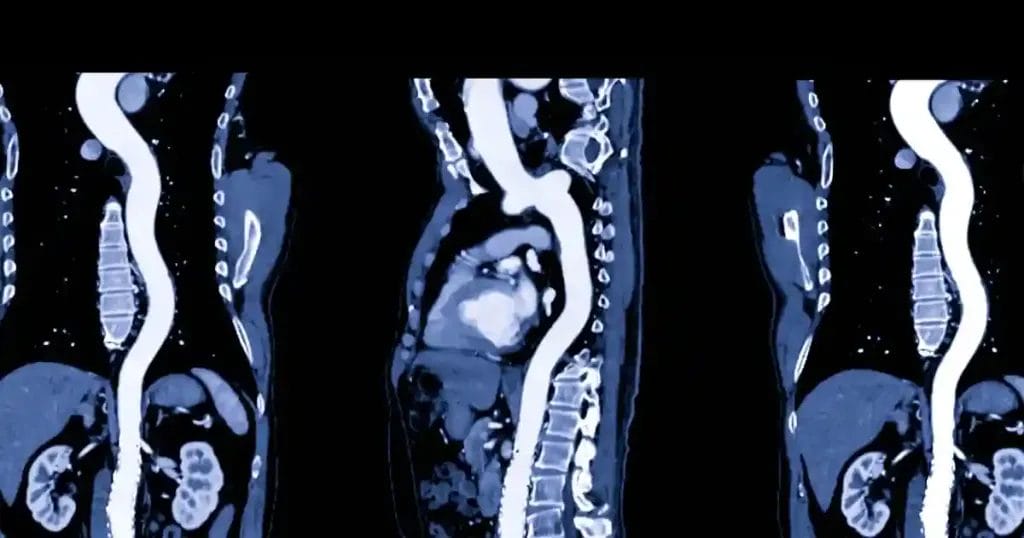

- التصوير المقطعي المحوسب (CT scan): يوفر صور مفصلة للشريان.

- الرنين المغناطيسي (MRI): حيث يتم تشخيص تمدد الشريان الأورطي عن طريق الرنين المغناطيسي الذي يوفر صور أكثر تفصيل لكل مكان في الشريان الأورطي ويوضح انسلاخ الشريان الاورطي

تمدد الشريان الأورطي البطني، هو حالة صحية خطيرة قد تهدد الحياة، لذا يجب التشخيص المبكر للحالة وعمل الأشعة المقطعية اللازمة لمعرفة حجم وشكل تمدد الأوعية الدموية، حيث أنه كلما زاد حجم تمدد الأوعية الدموية كلما زاد الخطر، وبذلك يمكن الوقاية من تمدد الشريان علاجه مبكرًا.